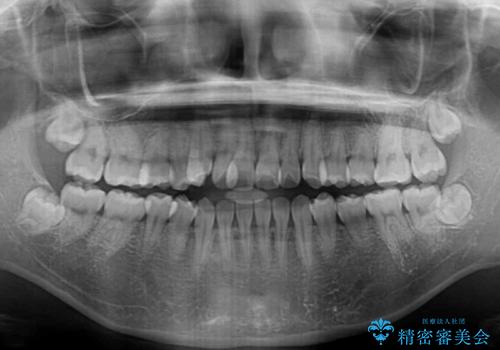

- 前歯の開咬と、上顎前歯の八重歯やデコボコを気にして来院された患者様です。

上顎歯列が狭窄していたため、急速拡大装置により上顎骨を側方に拡大し、その後ワイヤー装置にて矯正治療を行うこととしました。

上顎骨を拡大することで、八重歯やデコボコを歯列に収めることができ、下顎の歯が外に位置していた奥歯の咬み合わせも改善することができました。

スペースも短期間に獲得できるため、1年程度で治療を終えることができました。